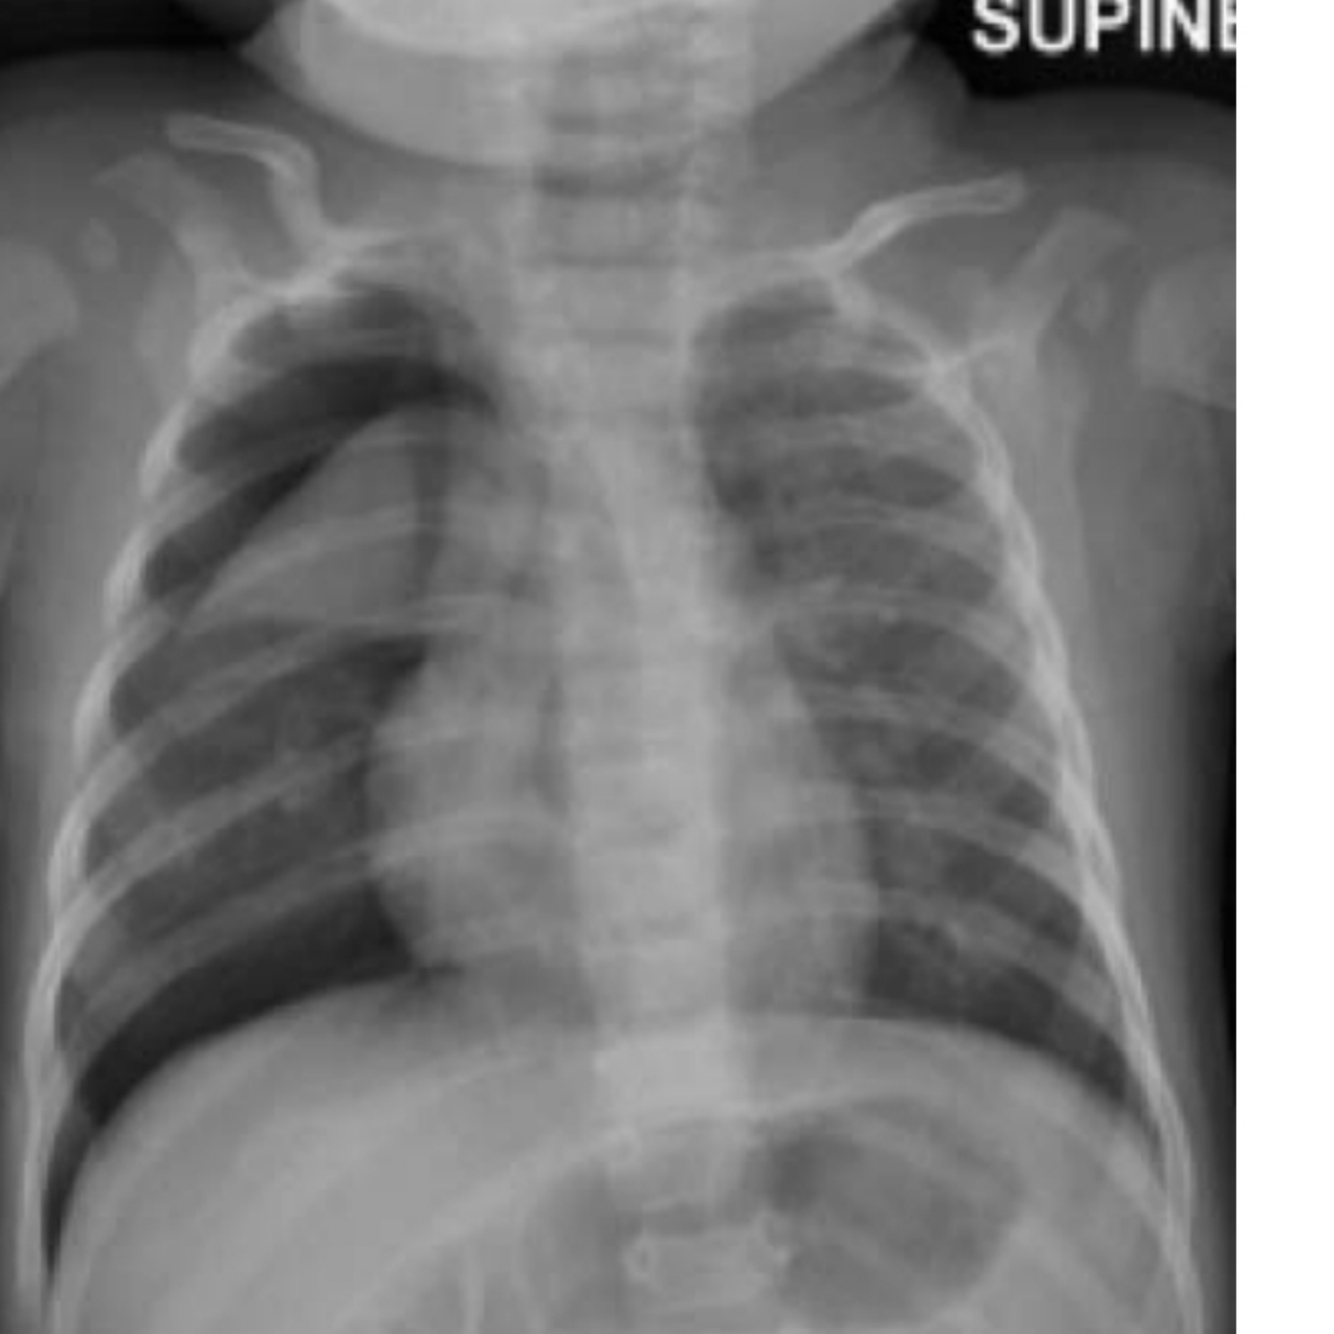

Q

An X-ray is done in recovery.

see Figure 2.3. What is your

diagnosis?

A

Barotrauma and right-sided pneumothorax with mediastinal shift.